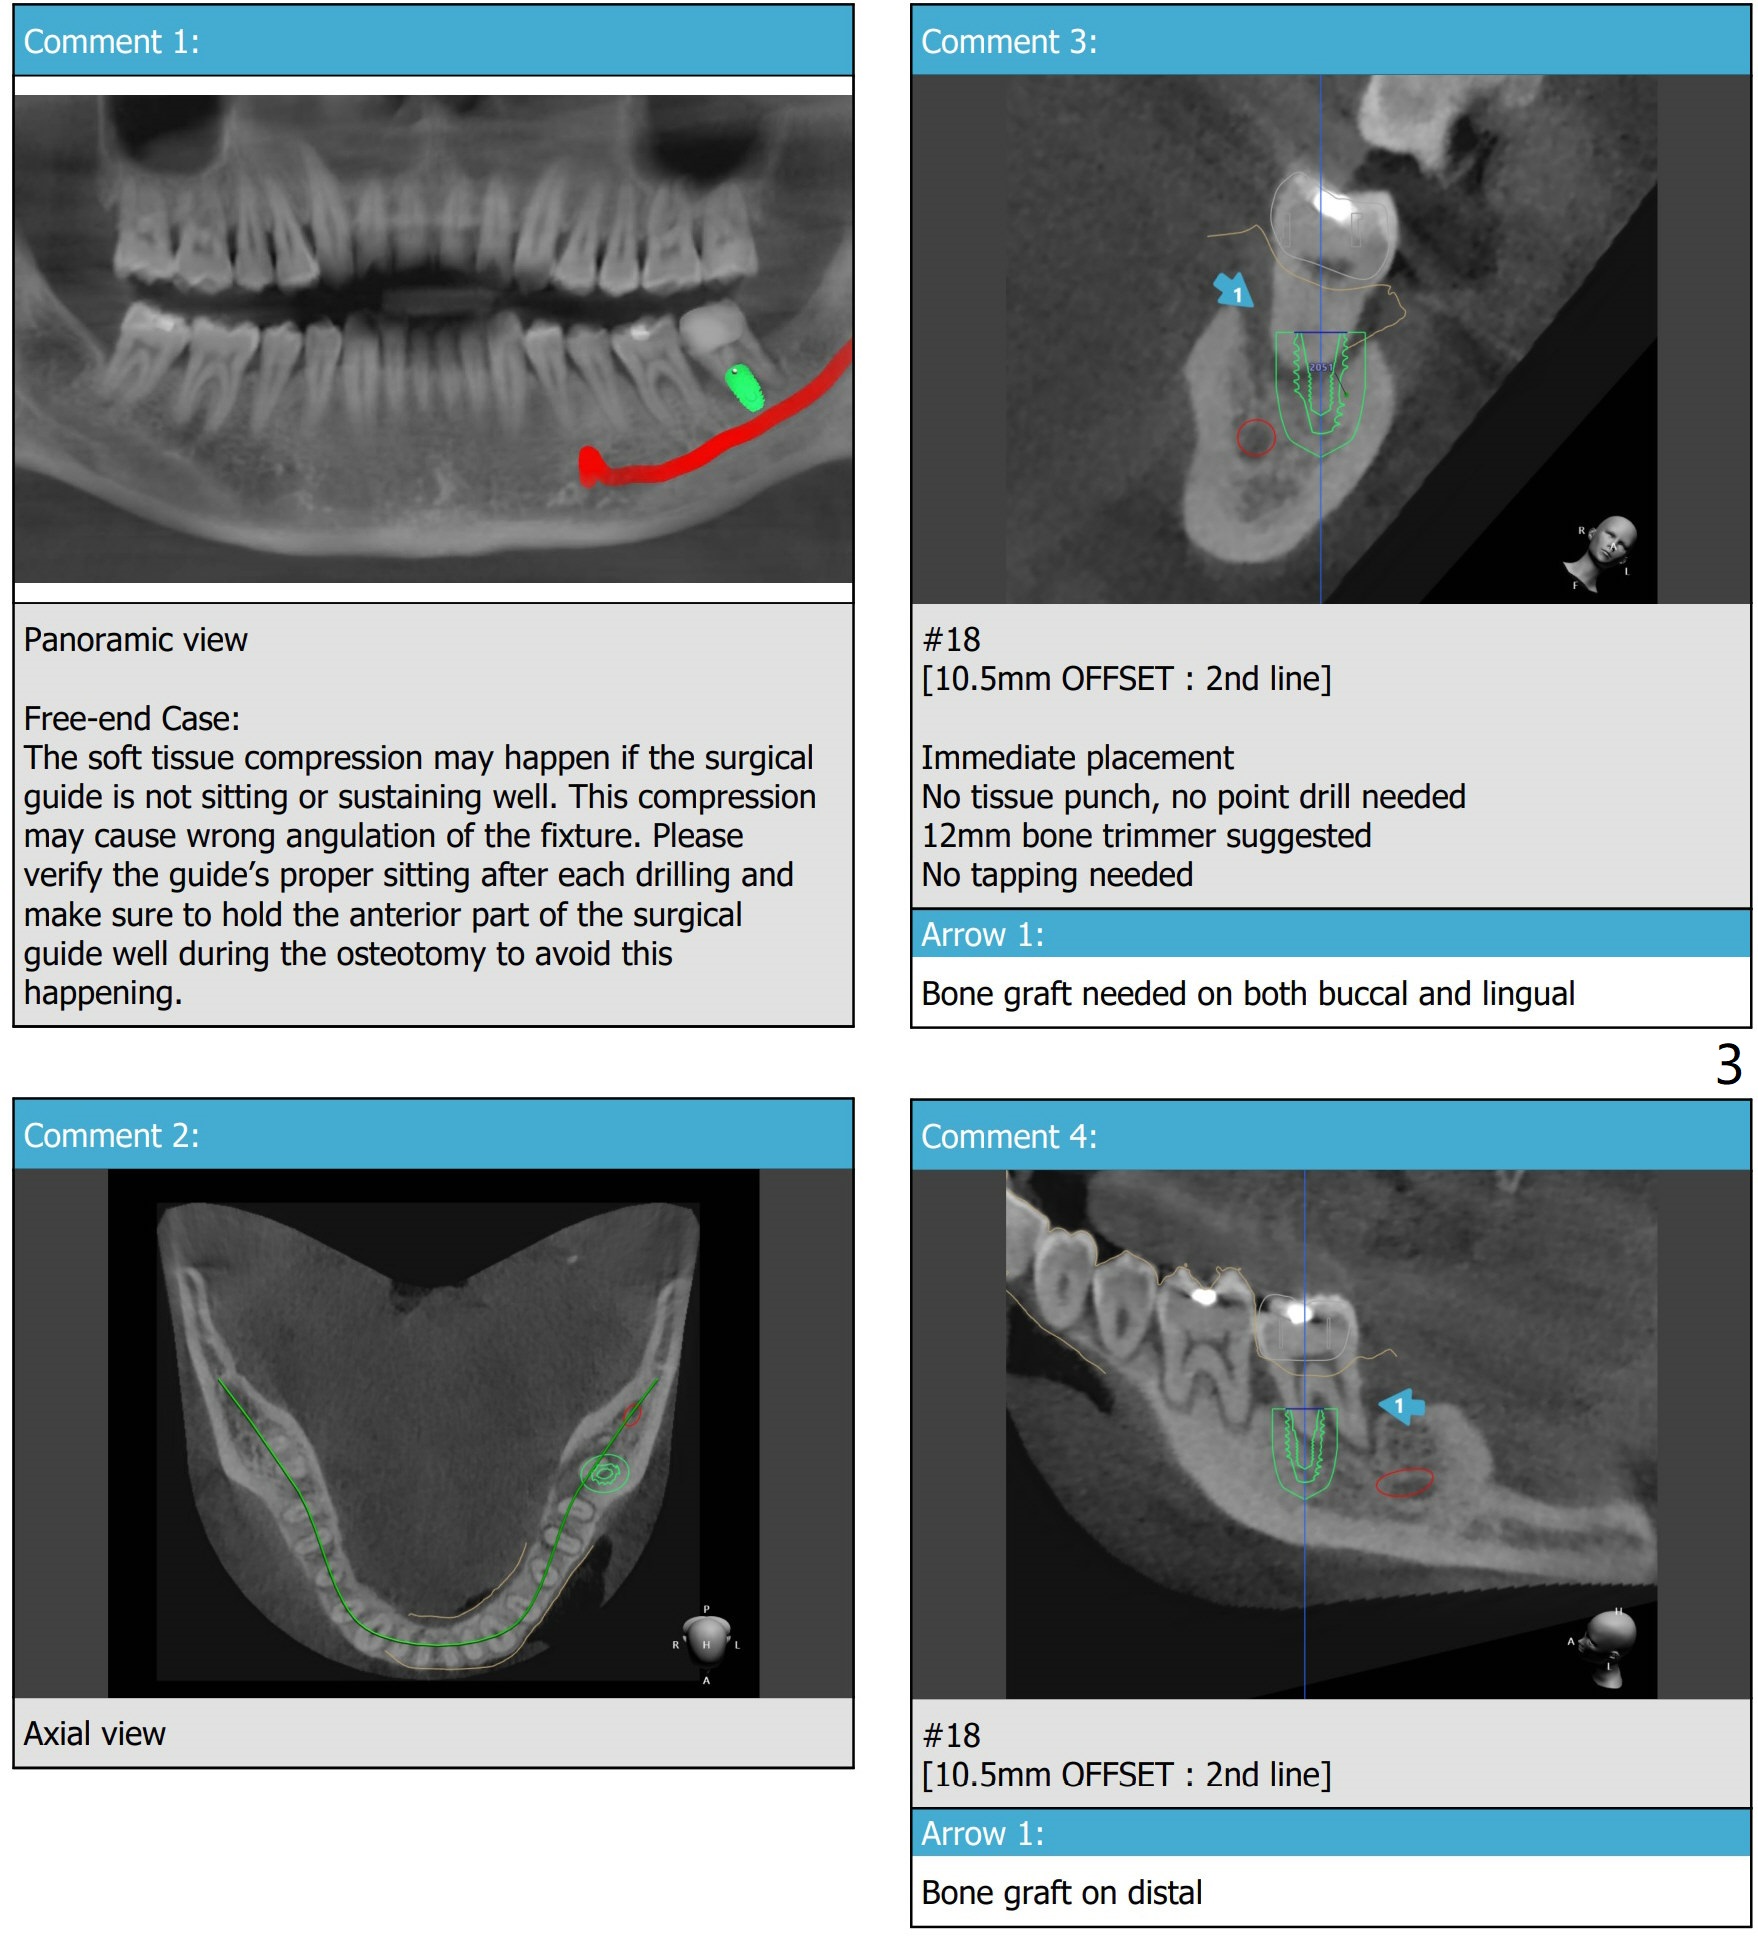

Xin Wei, DDS, PhD, MS 1st edition 04/07/2021, last revision 05/31/2021